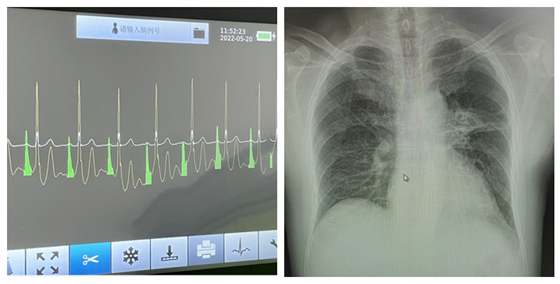

我院在此次B超引导结合心腔内电图定位技术的实施过程中,使用了先进的3CG技术,操作时通过心电图P波的波形和颜色变化,实时判断PICC导管的尖端位置,为安全置管和确定导管最佳位置提供保证。本案例患者,通过术后胸片定位确定导管尖端位于第八椎体上缘右侧水平,符合INS指南中推荐的最佳位置。

实时动态定位                                术后胸片